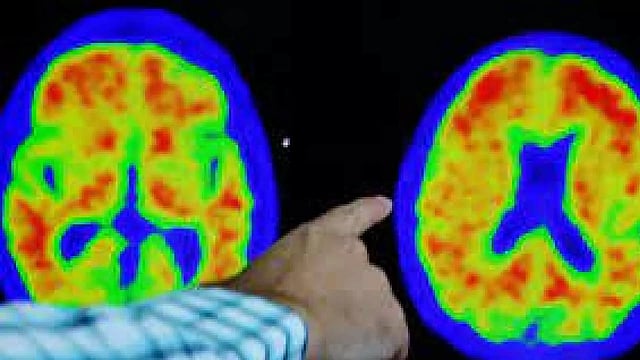

Representative Image (Photo/Reuters)

CHICAGO: Breakthrough Alzheimer's treatments that remove toxic proteins from the brain have revived interest in vaccines to treat the memory-robbing disease, potentially offering a cheaper, easy-to-administer option for millions of people, according to interviews with 10 scientists and company executives.